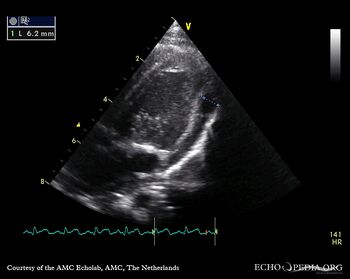

| Courtesy of: AMC Echolab, AMC, The Netherlands | |

| PSAX | |